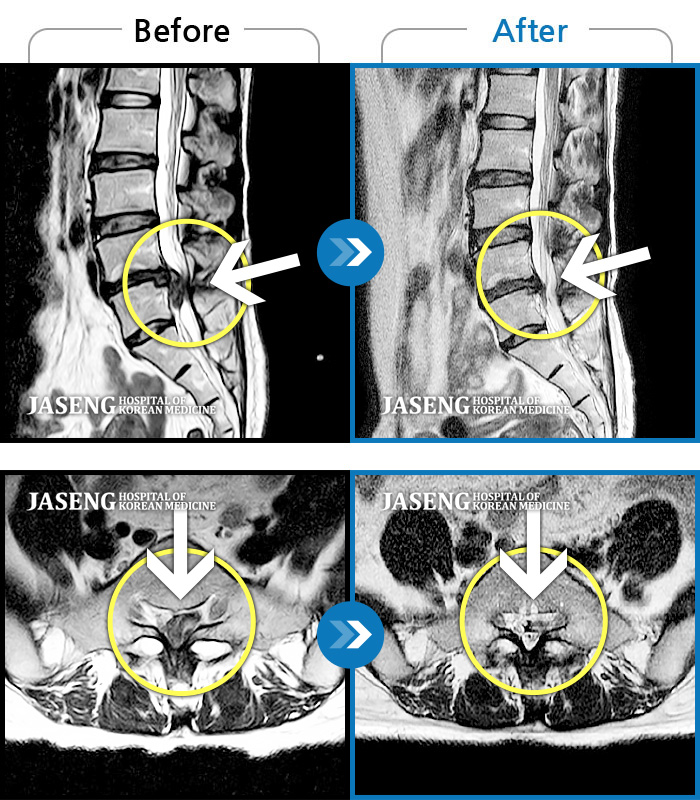

MRI 치료사례

허리통증, 골반 저림, 발가락 근력저하가 심하여 일상생활이 불가능한 상태